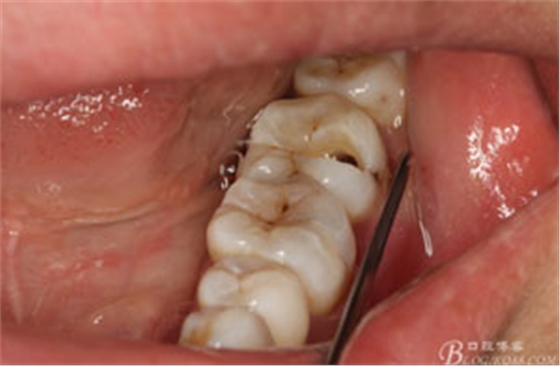

圖4.行下頜無痛阻滯麻醉

圖5.加局部浸潤麻醉